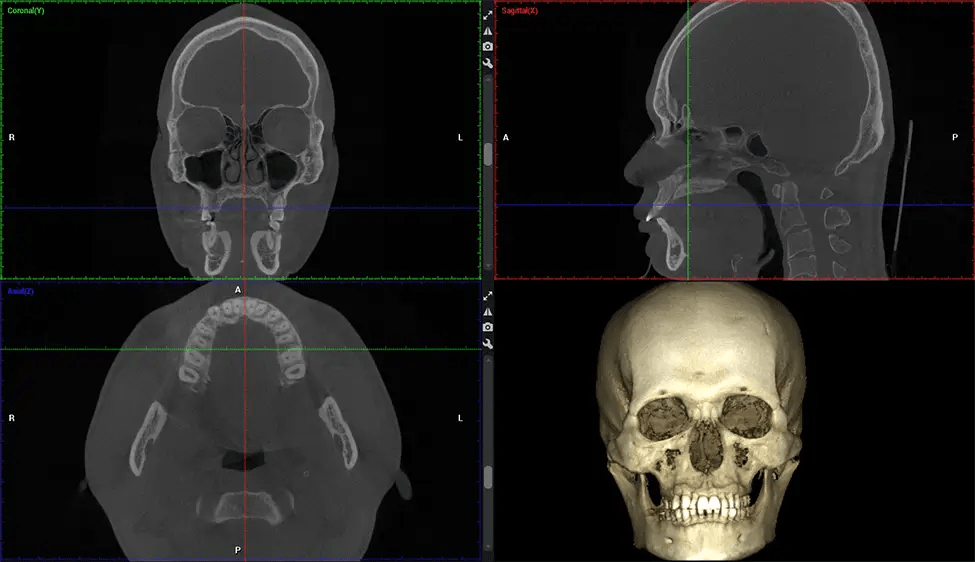

Esta exploración 3D, llamada tomografía computarizada de haz cónico, le brinda a su dentista una imagen más completa de su anatomía bucal y sus procesos patológicos que una radiografía tradicional. A diferencia de las radiografías convencionales, que capturan una imagen 2D de la boca desde varios ángulos, una exploración 3D toma varias radiografías digitales para una imagen. Proporciona una vista completa de la mandíbula, los dientes, los nervios y los tejidos blandos. Esta vista mejorada permite a los dentistas detectar problemas menores que no son visibles en las exploraciones 2D tradicionales, como muelas del juicio impactadas o fracturas óseas en la cavidad sinusal.

Existen muchos beneficios al utilizar la tecnología CBCT, especialmente en comparación con el formato tradicional de rayos X 2D. Una de las ventajas más importantes de las exploraciones CBCT es que proporcionan mucha más información que las radiografías tradicionales. Una exploración le permite a su dentista ver imágenes desde todos los ángulos de su mandíbula y boca, incluidos los senos nasales, la cavidad nasal, los pómulos y otras áreas circundantes. Esta información adicional ayuda a su dentista a elaborar un plan de tratamiento integral que aborde todos los aspectos de su salud bucal.

Después del proceso de escaneo, las imágenes de rayos X capturadas son procesadas por el software CBCT, que aplica algoritmos para reconstruir una imagen 3D detallada del área escaneada. El software recopila estas imágenes de rayos X individuales y crea una representación digital en 3D de la anatomía del paciente. El dentista o el radiólogo pueden ver y analizar la imagen CBCT 3D reconstruida. Esta imagen se puede manipular, rotar y acercar o alejar para examinar estructuras específicas y evaluar la condición del paciente.

Planmeca Viso G7 CBCT (Cone Beam CT Scan) está diseñado para superar las demandas de los líderes de la industria, los especialistas y las grandes instituciones. Tiene un gran sensor de ø25×30 cm con cuatro cámaras integradas. Puede capturar tamaños de volumen ilimitados, desde ø3×3 cm hasta ø30x30cm, capturando el casquete escutelario a través de C7 en la columna cervical. Planmeca Viso G7 ofrece el escaneo de volumen único más grande de la industria de ø30×19 cm. Está preparado para manejar modalidades de imágenes avanzadas como la tecnología Planmeca ProFace® y Planmeca 4D™ Jaw Motion. El soporte occipital para la cabeza permite una visión sin obstáculos del tejido facial.